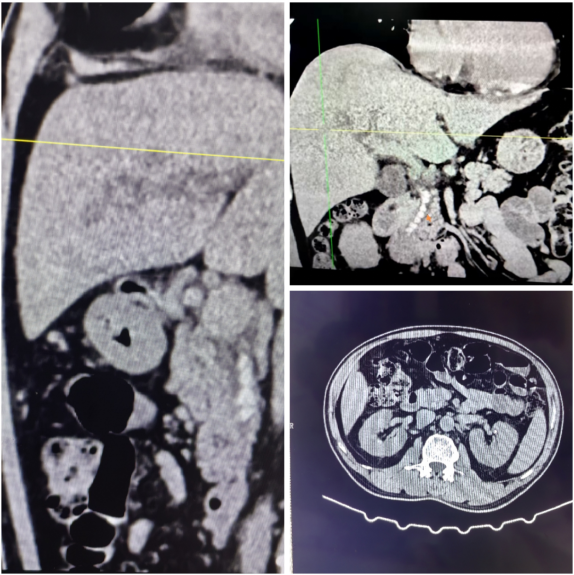

患者因上腹剧痛、皮肤眼睛发黄入院,

经检查确诊为:感染性休克、急性化脓性胆管炎、梗阻性黄疸、胆总管结石、急性化脓性胆囊炎、糖尿病,病情危急!

化脓性胆管炎可不是小病——胆管里细菌疯狂繁殖,胆汁淤堵成“毒窝”,会引发感染性休克、肝衰竭、多器官衰竭,甚至猝死!

幸好及时就医,做了腹腔镜胆囊切除术、胆总管切开术、胆道镜取石术、T管引流术、腹腔引流术的微创手术。

一次性解决胆囊和胆管结石,把“毒源”彻底清除。手术顺利,现在术后恢复中~